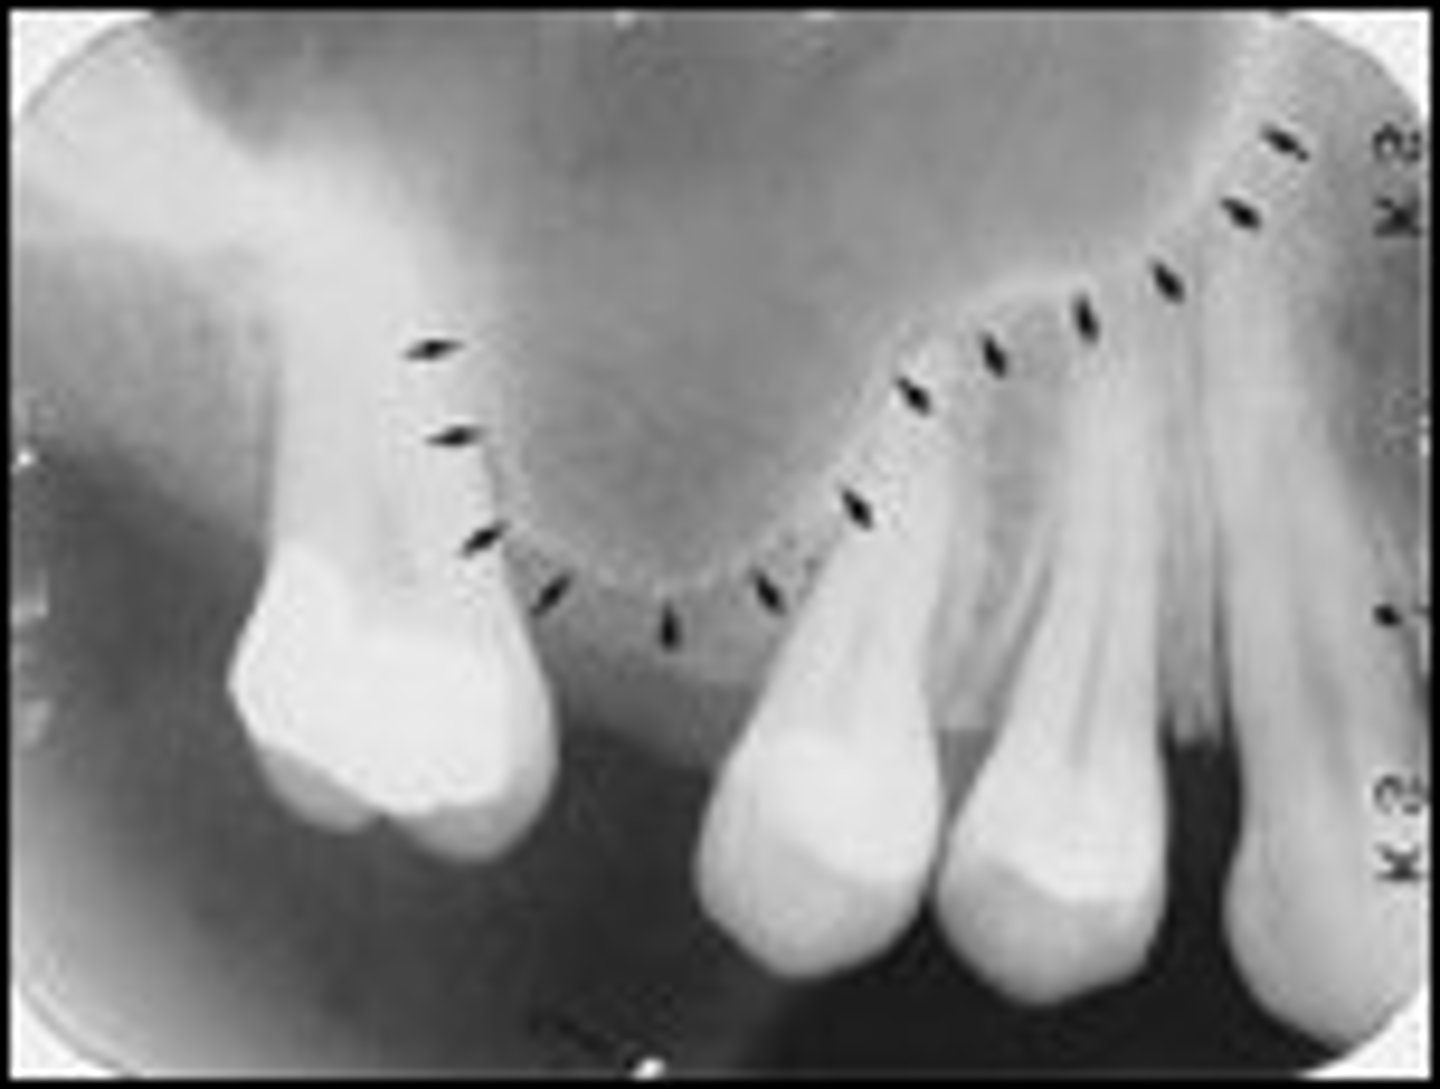

what are the landmarks seen in maxillary radiographs

max sinus, max tuberosity, zygomatic process, nasal sinus, nasal septum, lateral fossa, medial paltine suture

where can you see the max sinus in a radiograph

apices of max molars

where can you see the max tuberosity in a radiograph

18/28 area

where can you see zygomatic process in a radiograph

where can you see the nasal sinus in a radiograph

apices of 11/21

where can you see the nasal septum in a radiograph

where can you see the lateral fossa in a radiograph

between lateral and canines

where can you see the median palatine suture in a radiograph

line running the length of a palate

does the maxillary sinus appear radiolucent or radiopaque in a radiograph

radiolucent

does the maxillary tuberosity appear radiolucent or radiopaque in a radiograph

radiopaque

does the zygomatic process appear radiolucent or radiopaque in a radiograph

does the nasal sinus appear radiolucent or radiopaque in a radiograph

does the nasal septum appear radiolucent or radiopaque in a radiograph

does the lateral fossa appear radiolucent or radiopaque in a radiograph

does the median palatal suture appear radiolucent or radiopaque in a radiograph